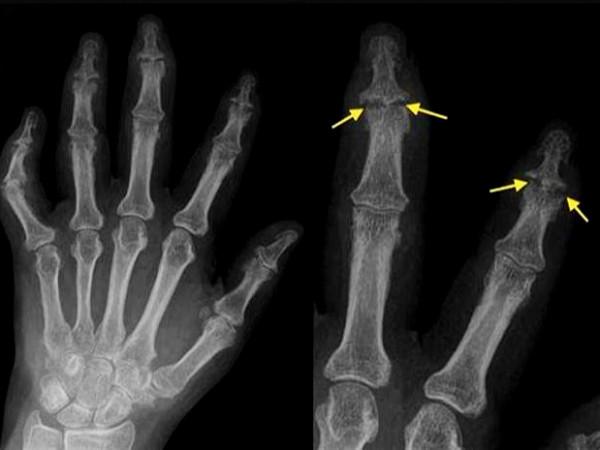

另外當患者患有骨關節炎的時候,早期會在手指的遠端有一些特殊的改變,在患者的手指遠端關節處會出現一些小的結節,觸碰會有疼痛感,但如果不過度觸碰是沒有任何感覺的,在早期的時候甚至拍片子也發現不了明顯的骨關節改變,這種情況,我們稱之赫伯登結節,往往預示著患者身體存在著骨關節炎,也預示著手部將要出現比較明顯的骨關節炎改變。

診斷:如果存在著手部僵硬、疼痛,活動受限,出現了赫伯登結節,那麼應該高度可疑存在著骨關節炎,診斷往往要進行手部的x線檢查,可以發現手指關節間隙的狹窄,可以發現輕度的骨質增生或者是嚴重的骨質增生。也可以進行風溼4項化驗,排除是否存在著痛風、風溼病或者是類風溼相關疾病。